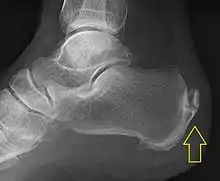

Calcification deposits forming an enthesophyte within the Achilles tendon at its calcaneal insertion. The Achilles tendon is wider than normal, further suggesting inflammation.

Achilles tendinitis is usually diagnosed from a medical history, and physical examination of the tendon. Projectional radiography shows calcification deposits within the tendon at its calcaneal insertion in approximately 60 percent of cases.[17] Magnetic resonance imaging (MRI) can determine the extent of tendon degeneration, and may show differential diagnoses such as bursitis.[17]